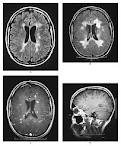

La esclerosis múltiple (EM) es una enfermedad que afecta a la mielina o materia blanca del cerebro y de la médula espinal, provocando la aparición de placas escleróticas que impiden el funcionamiento normal de esas fibras nerviosas. La mielina es una sustancia grasa que rodea y aísla los nervios, actuando como la cobertura de un cable eléctrico y permitiendo que los nervios transmitan sus impulsos rápidamente. La velocidad y eficiencia con que se conducen estos impulsos permiten realizar movimientos suaves, rápidos y coordinados con poco esfuerzo consciente.

Desde 1920 se ha descrito la euforia como un síntoma frecuente en la EM, alteración observable hasta en un 25% de los pacientes. Se trataría de "un ánimo de complacencia que está fuera de contexto de su situación total", sin acompañarse del correlato neurovegetativo necesario para diagnosticar un trastorno afectivo de tipo maníaco. Los pacientes eufóricos tendrían más frecuentemente compromiso cerebral, dilatación ventricular, peor función cognitiva, peor función neurológica y mayor incapacidad social que los que no tienen este síntoma.